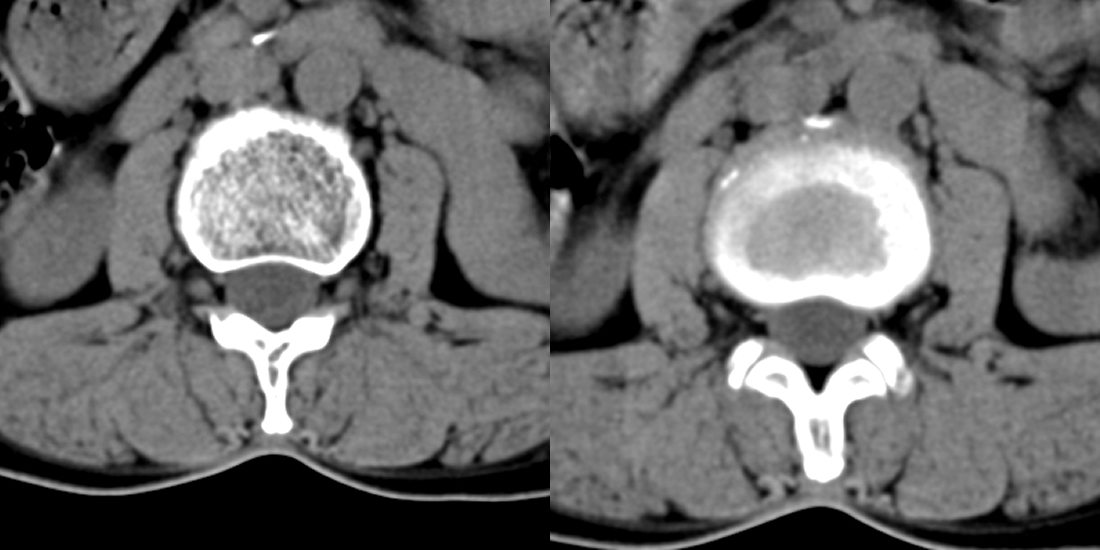

52岁女性,腰痛,活动守限,有腰部外伤史。请教各位战友,应该怎么报。

l2/3椎间隙